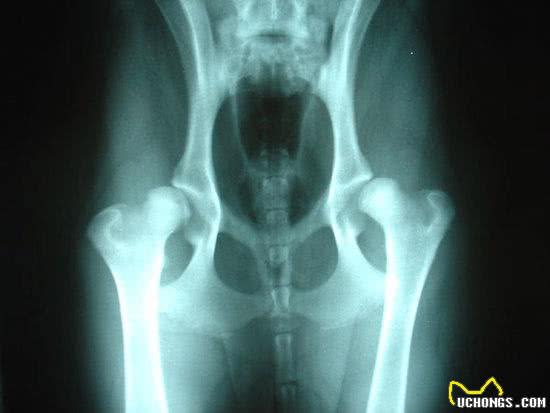

X光显示一条拉布拉多犬髋关节异常/网易沸点杂家

根据美国宾夕法尼亚大学学者David的研究数据:狗的重心靠近前肢,在心脏附近。正常的姿态下,狗的前腿承担了自身重量的60%。

也就是说,狗狗的后腿其实很脆弱,这也是大多数狗的后腿比前腿细很多的原因。

身体结构决定了狗狗需要用四肢同时行走,如果身体全部重量长时间压迫在脆弱的后腿上,会引起关节炎症、软骨受损、髌骨脱位等疾病。

狗的体重越大,这样的后果越严重。

若是狗狗的胸腰椎疾病影响了排尿功能,48小时不缓解,就会引发尿毒症。椎间盘突出造成的四肢瘫痪,则会永远剥夺狗狗自由奔跑的权利。